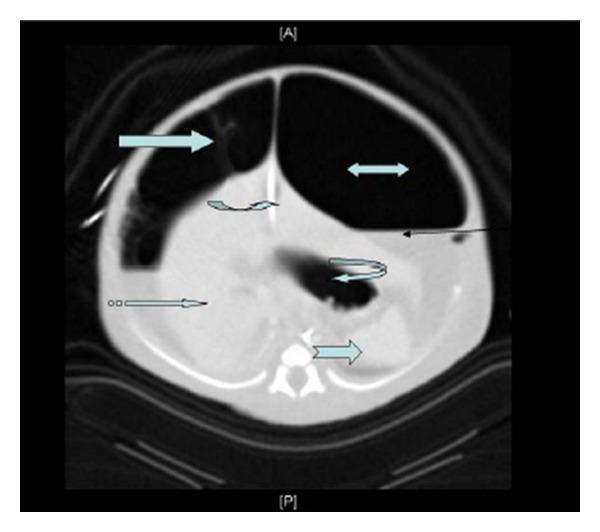

Meconium peritonitis pseudo-cyst is very rare. Its perinatal management is controversial and can be associated with increased fetomaternal morbidity and mortality. A 34-week gestation infant with large meconium peritonitis pseudo-cyst, detected by intrapartum fetal ultrasound study, had abnormally increased ratio of fetal abdominal circumference to head circumference. Intrapartum aspiration of the pseudo-cyst was performed and was followed by a smooth vaginal delivery. The postnatal course of the baby showed that early laparotomy was essential for stabilisation of the infant's general condition.

胎粪性腹膜炎假性囊肿非常罕见。其围产期管理存在争议,且可能增加母婴发病率和死亡率。一名34周妊娠的婴儿,通过产时胎儿超声检查发现患有巨大胎粪性腹膜炎假性囊肿,其胎儿腹围与头围之比异常增加。对假性囊肿进行了产时抽吸,随后顺利经阴道分娩。婴儿的产后病程表明,早期剖腹手术对于稳定婴儿的一般状况至关重要。